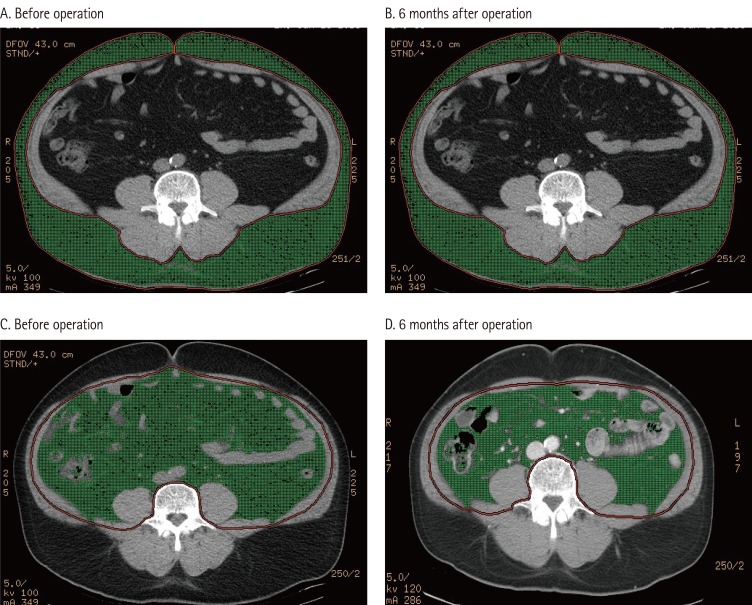

Changes in Fat Intake, Body Fat Composition and Intra-Abdominal Fat after Bariatric Surgery

Clinical Nutrition Research 2014;3(2):157-161.